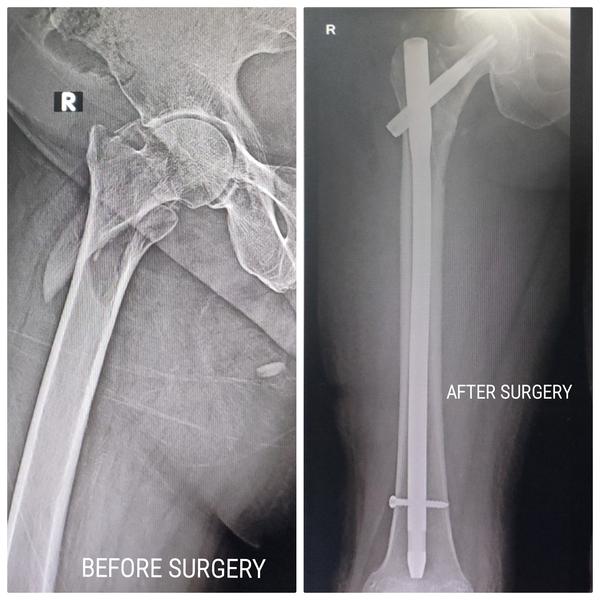

Joint reconstruction surgery is a valuable option for individuals who are experiencing joint pain and dysfunction due to various factors, including aging, wear-and-tear, or injuries. When less invasive treatments like injections and physical therapy are no longer effective, joint reconstruction surgery can provide relief and improve the quality of life.Total Knee Replacement (TKR):Total Hip Replacement (THR)Total Shoulder Replacement (TSR):Total Ankle Replacement (TAR):Elbow Replacement Surgery:Hand and Wrist Joint Reconstruction

Your hips play a crucial role in your daily life, and when arthritis or a hip injury strikes, it can hinder your ability to perform everyday tasks. Severe hip pain, especially while sitting or trying to sleep, can significantly impact your quality of life. In such cases, a Total Hip Replacement may be the most viable option to alleviate pain and restore your normal activities.If you and your healthcare provider determine that a total hip replacement is the best course of action for your condition, the following information will help you gain a better understanding of what to anticipate. Total hip replacement surgery entails the removal of damaged bone within the hip joint and its replacement with a prosthetic implant. This artificial joint, also referred to as a prosthesis, not only prevents bone-on-bone contact but also re-establishes a smooth and pain-free hip joint.